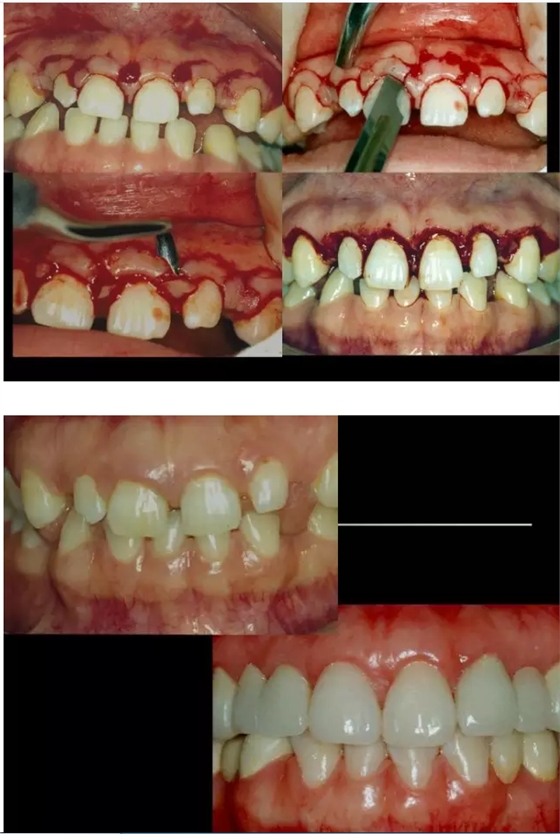

【牙科知識(shí)】牙周病相關(guān)手術(shù)圖解,非醫(yī)學(xué)專業(yè)勿點(diǎn)